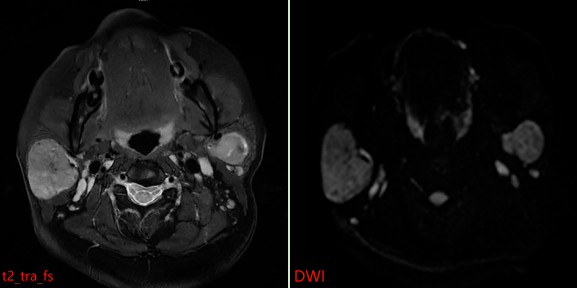

MR表现:双侧腮腺浅叶下极见结节状略混杂信号,T1以低信号为主、T2以 稍高信号为主,DWI呈稍高信号,ADC图呈稍低信号,边界清晰,增强扫描病变中等强化,强化较均匀,其内见点状无强化影。